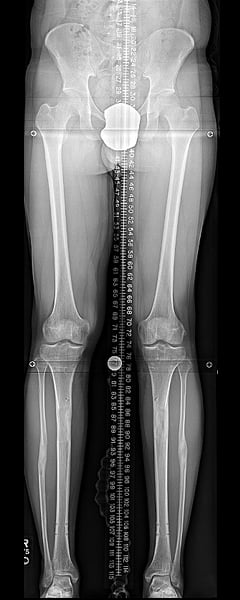

Femurs at end of consolidation.

Femurs with nails removed.

Tibia at end of consolidation.

Tibias with nails removed.How much taller can stature lengthening surgery make you?

The most common increase in height is three inches (or 8 cm) because that is how long the implanted rods extend. If the procedure is repeated in the lower leg bone (the tibia), another 2 to 3 inches can be obtained, for a total of about 5 to 6 inches of added height.

Lengthening three inches is approximately a six-month process. Following surgery and short rest period, the bones are lengthened by less than 1mm (less than 0.04 inches) per day, and the lengthening portion of the treatment takes 3 to 4 months. The bones then take another 6 to 8 weeks to heal and then normal activity can resume. The lengthening rods are removed around 12 months after the initial surgery.